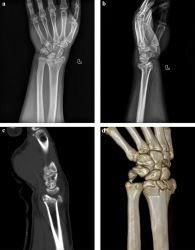

Need specialized care for complex fractures? We provide Advanced Intra-Articular Fracture Care Available in Kota with modern techniques and skilled orthopedic doctors. Our treatments aim for precise bone healing, joint stability, and early rehabilitation to restore full function. With personalized attention and advanced orthopedic facilities, we ensure faster recovery and improved quality of life. Trust our experts in Kota for effective fracture treatment and orthopedic support.